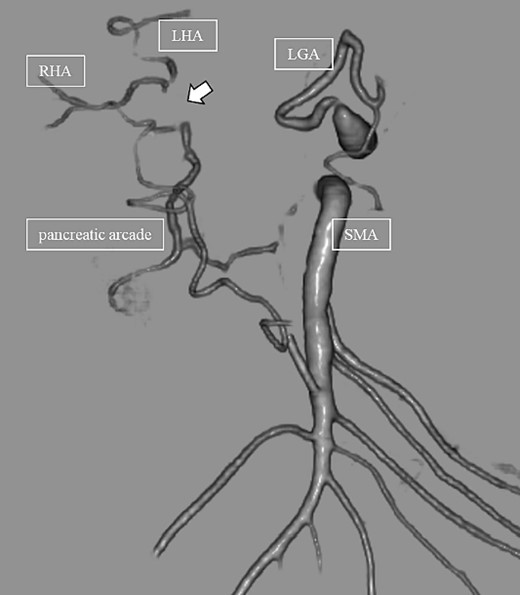

Subsequently, interventional radiology (IVR) was performed. However, because the inferior pancreaticoduodenal artery (IPDA) was very narrow, the microcatheter could not be followed, and hemostasis with IVR was difficult. Therefore, on POD 48, relaparotomy pseudoaneurysm repair was performed. The abdomen was opened through an inverted L-shaped incision, and adhesiolysis was performed, after which a pseudoaneurysm was revealed at the junction of the GDA and PHA. Four transfixing sutures with 3–0 prolene were used. After confirming that the liver blood flow was maintained, surgery was completed. However, bloody drainage from the drain was observed on POD 56. CeCT revealed a pseudoaneurysm (Fig. 3A and B). IVR was considered difficult because of the narrow blood vessels; therefore, the patient underwent a second laparotomy for hemostasis. A pseudoaneurysm was further observed at the junction between the GDA and PHA. In this operation, we used deeper and wider penetrating sutures than in the previous surgery to completely halt blood flow in the GDA. We confirmed that the blood flow to the liver was maintained; however, it was deemed weak. The patient had an uneventful postoperative course without bleeding, and CeCT performed on POD 61 confirmed the disappearance of the pseudoaneurysm. Although the blood flow in the PHA could not be confirmed, the right and left hepatic arteries were preserved (Fig. 4). On POD 76, CT revealed no liver abscesses or infarctions. The drain was removed on POD 78, and the patient was finally discharged on POD 107 without rebleeding or liver failure.

(A, B) CT on postoperative Day 56. Contrast-enhanced CT shows a pseudoaneurysm at junction of the GDA and PHA (arrow).

CT on postoperative Day 61. Although blood flow in the PHA could not be confirmed (arrow), the right and left hepatic arteries are preserved.